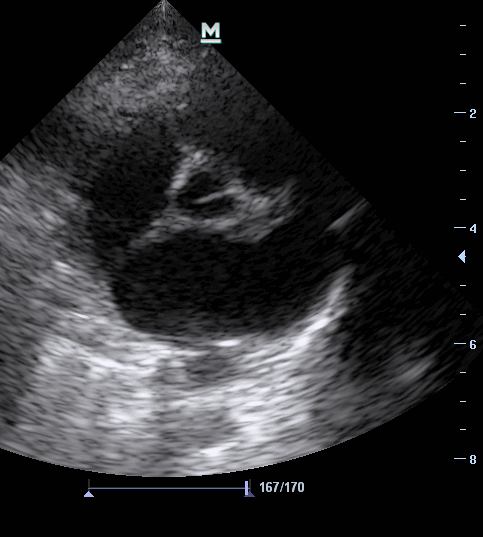

Рис. 2. Эхокардиография, В-режим. Визуализация аорты, дилатированного левого предсердия